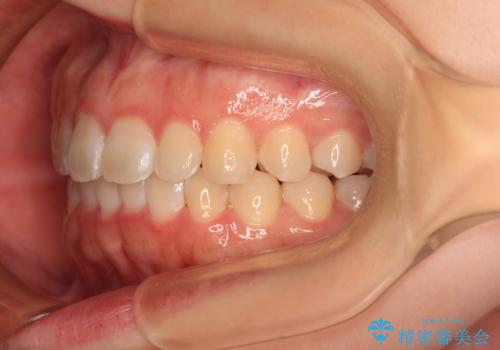

前歯のデコボコを整える インビザラインによる矯正治療

- 上下前歯のデコボコを気にして来院された患者様です。

叢生は軽度であり、ワイヤー矯正でもマウスピース矯正でも対応可能であったので、好きな装置を選んでもらいました。

相談の結果、インビザラインによる矯正治療を行うこととしました。

毎日の装着時間をしっかりと守っていただいたことで、1年程度で無事に治療を終えることができました。